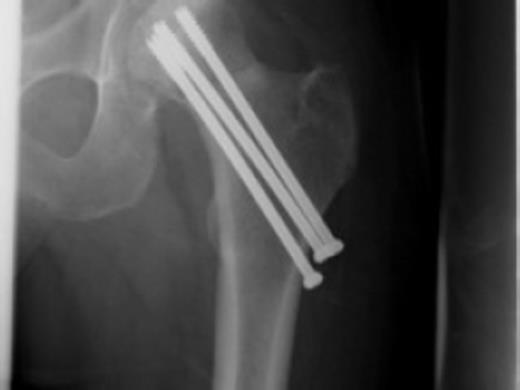

Postoperative care included early-supervised non-weight bearing mobilization for three months. Radiographs at three months showed no early displacement or evidence of avascular necrosis (Fig. 4). The patient progressed to protected full-weight bearing for a further three months.

At one year the patient was walking with a stick and mild limp, he had ninety degrees of hip flexion with limited internal and external rotation. Plain radiographs at this stage confirmed the fracture to be united with no evidence of avascular necrosis. The patient remained on yearly review and continued to function well. He returned to hobbies such as fishing and shooting and was pain free at three and a half years. The most recent review at four and a half years confirmed the presence of avascular necrosis (Fig. 5) however from a symptomatic point of view he is still able to maintain an active lifestyle with little pain.